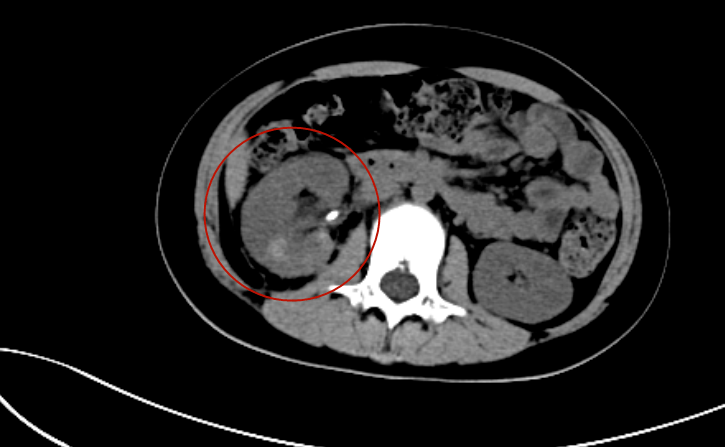

后车把手撞击腰部出现疼痛三小时来我院就诊,行ct检查提示右肾破裂,伴